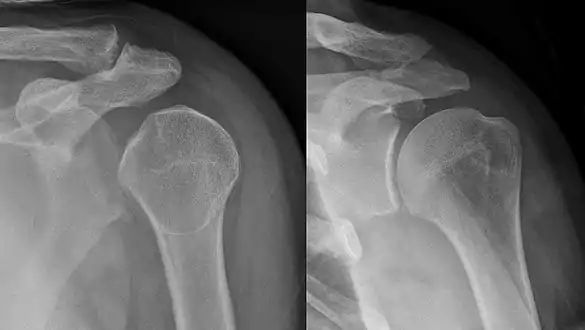

An anterior dislocation of the shoulder

Anterior dislocation of the right shoulder. AP X ray

Anterior dislocation of the right shoulder. Y view X ray.